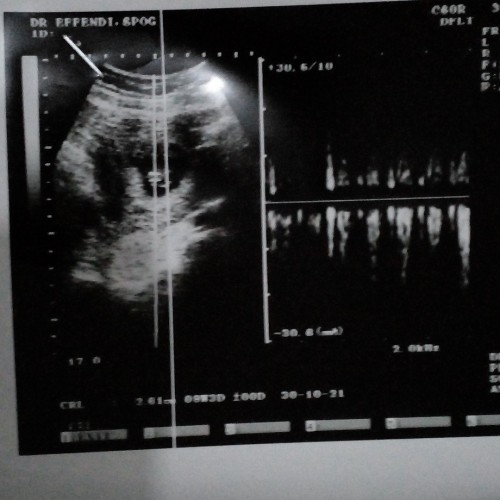

alhadulilah saya usg 6w2d udh kelihatan janinnya ☺️

ini saya udh usia kandungan 6w 3d bun,cb tranvaginal aj

saya USG 8 week udah ada janin dan ddj nya bun

aku 9w udah ada djj dan janinnya bun ☺